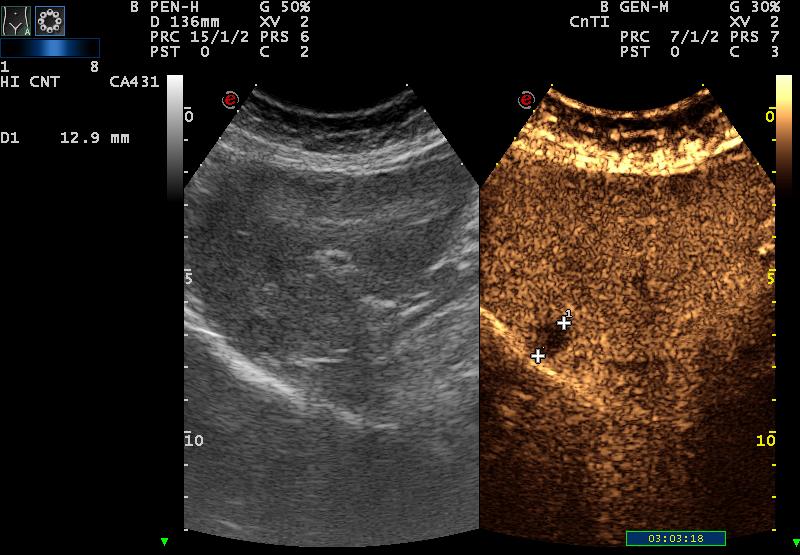

| CEUS over 2 min: total wash out |

| second metastasis |